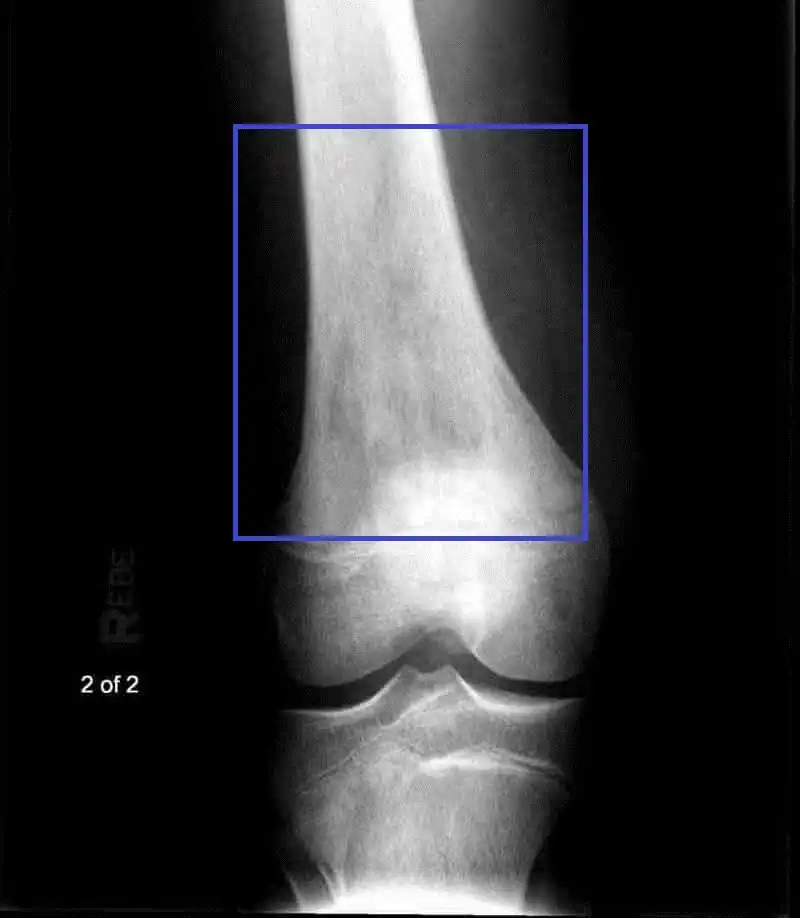

Intramedullary osteosarcoma of distal femur Intramedullary osteosarcoma of distal femur

Fig. 2 AP and lateral view of knee showing intramedullary osteosarcoma of distal femur.